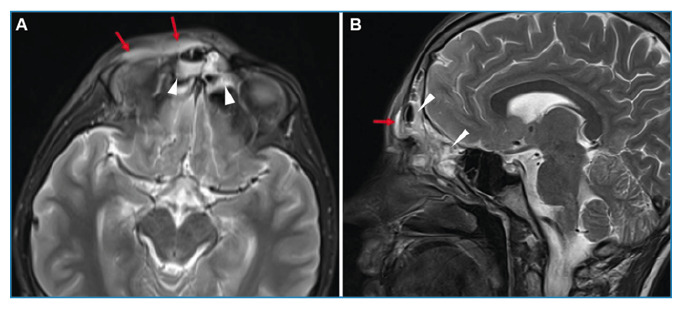

Widespread Encephalitis Following Acute Sinusitis in a Pediatric Patient.